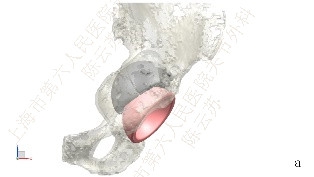

上海市第六人民医院关节外科陈云苏教授团队运用3D打印技术,通过与产品设计和加工工厂合作,术前采用CT对患者进行影像学数据采集,结合多孔钛表面技术,在全方位直视下“量体裁衣”地制定出个体化人工垫块设计和手术方案,成功治疗了两例有严重髋臼侧骨缺损的髋关节翻修患者。

图2

患者。女性,65岁,左全髋关节置换术后18年,疼痛12年,加剧2年。图1:术前,图2:CT模拟设计,图3:3D打印模块,图4:术中缺损填充,图5:术后片,图6:术后1年随访片